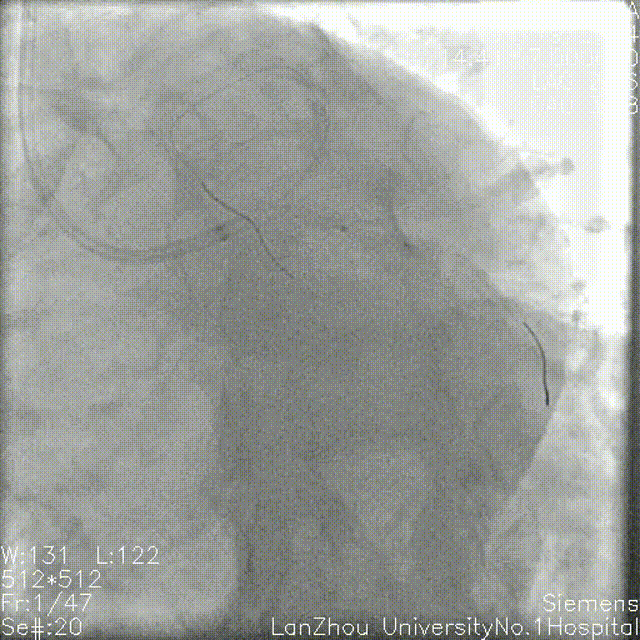

头位造影:

LM较短,末端可见重度狭窄,前降支近中段全程弥漫性狭窄伴钙化;

回旋支次全闭,可见钙化影。

右肩造影:

前降支近中段全程弥漫性狭窄伴环形钙化,最重处95%狭窄;

对角支开口狭窄不重,角度不大,可能不需要导丝保护。

蜘蛛位造影:

左主干开口、体部未见明显狭窄;

第一对角支开口重度狭窄;

回旋支次全闭,开口、近端、中段重度狭窄,可见环形钙化。